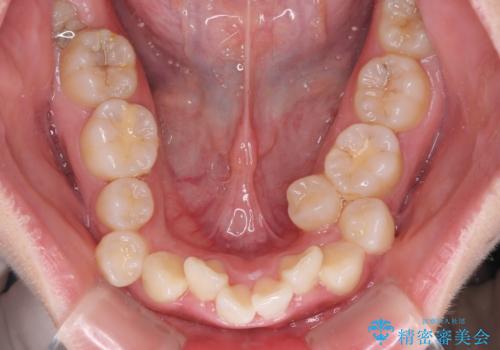

- 上下の八重歯やデコボコを気にして来院された患者様です。

上下ともに八重歯が顕著であったので、上下左右第一小臼歯4本を抜歯し、補助装置を使用して速やかに改善しながら、ワイヤー装置にて矯正治療を行うこととしました。